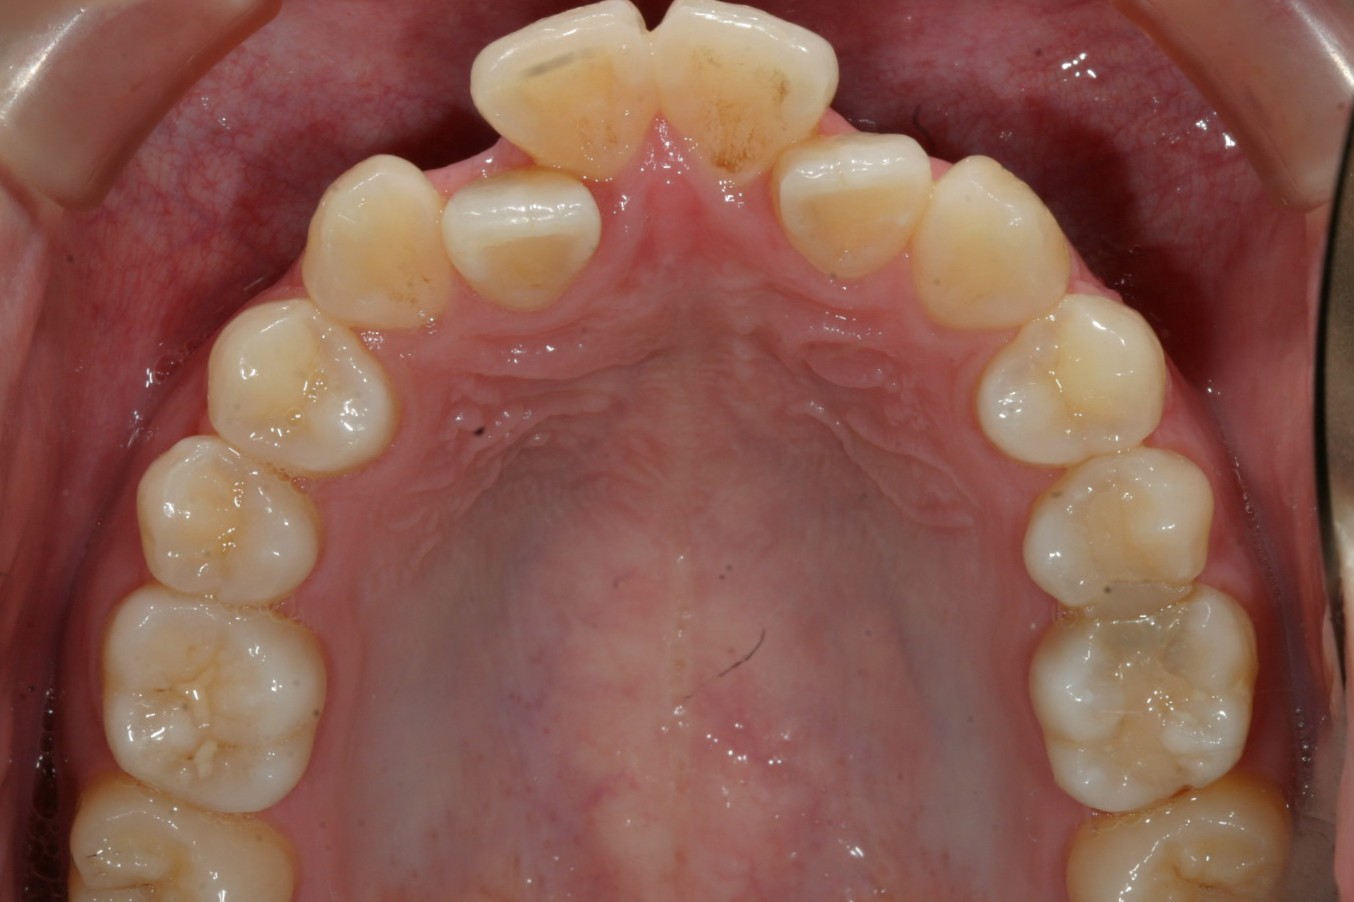

前歯がすごく飛び出てガタついています。

上顎の割に下顎の叢生は臼歯部に乱れがあります。